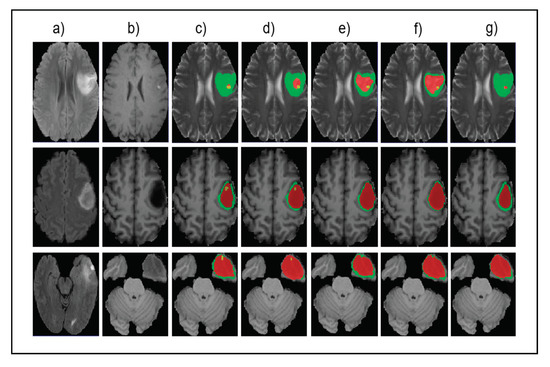

Figure 5 shows the input images, ground truth, and segmentation results of the enhancing tumor predicted by four models including our model, ReversibleUnet [48], No New-Net [49], and DMFNet [43]. As shown in the first row of the figure, ReversibleUnet and No New-Net predicted high false negatives on the enhancing tumor (yellow color), DMFNet failed to segment the enhancing tumor area while our model can accurately segment them. In the second and third rows of Figure 5, we can see that our model could segment the area of small enhancing tumor while other models failed to segment them. Figure 6 shows the dice similarity coefficient (DSC) stratified by tumor size.

Figure 5.

Qualitative comparison of different models for small tumor segmentation. (a) Input fluid attenuated inversion recovery (FLAIR) image. (b) Input T1 image and (c) ground truth images. (d) Results of our method. (e) Results of ReversibleUnet [48]. (f) Results of No New-Net [49]. (g) Results of DMFNet [43].